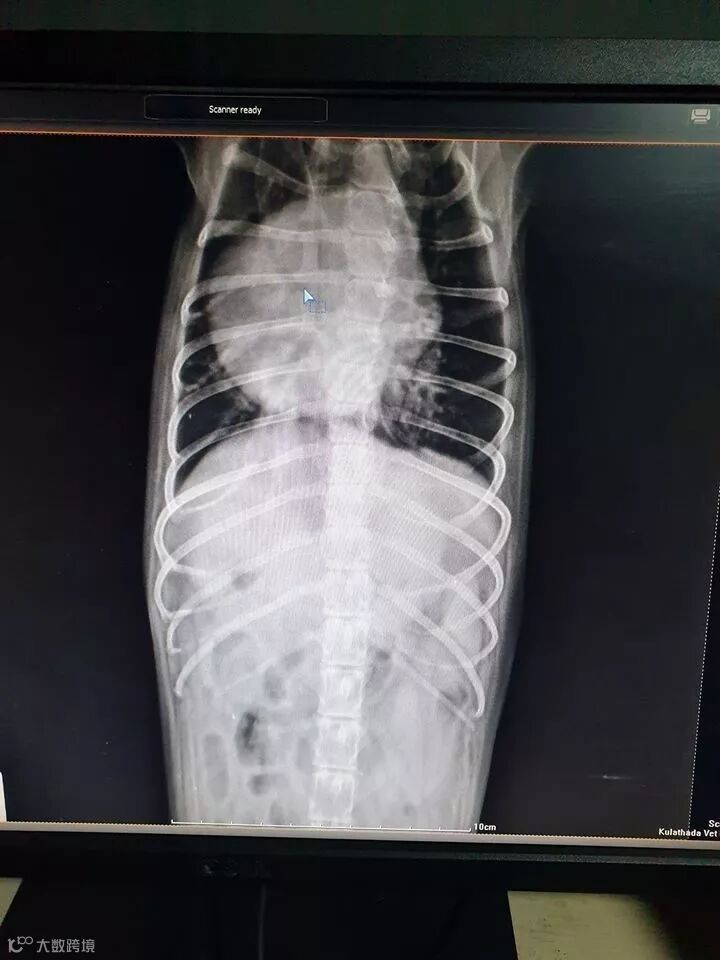

该网友称,这两天家里的狗狗一直在干咳,带它去看兽医,抽血、拍X光,检查结果发现狗狗竟然发炎了,医生表示狗狗可能患上了慢性阻塞性肺疾病,不过好在狗狗没有发烧、也没有出现呼吸急促的现象,所以病情还没那么严重,先吃药治疗咳嗽和炎症;他还表示导致爱狗生病的就是PM2.5,因为它直接影响到了肺和心脏,庆幸的是及时带狗狗去就医了。